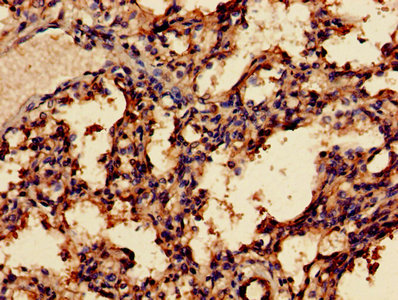

Immunohistochemistry of paraffin-embedded human breast cancer using CSB-PA013334LA01HU at dilution of 1:100

Immunohistochemistry of paraffin-embedded human lung tissue using CSB-PA013334LA01HU at dilution of 1:100